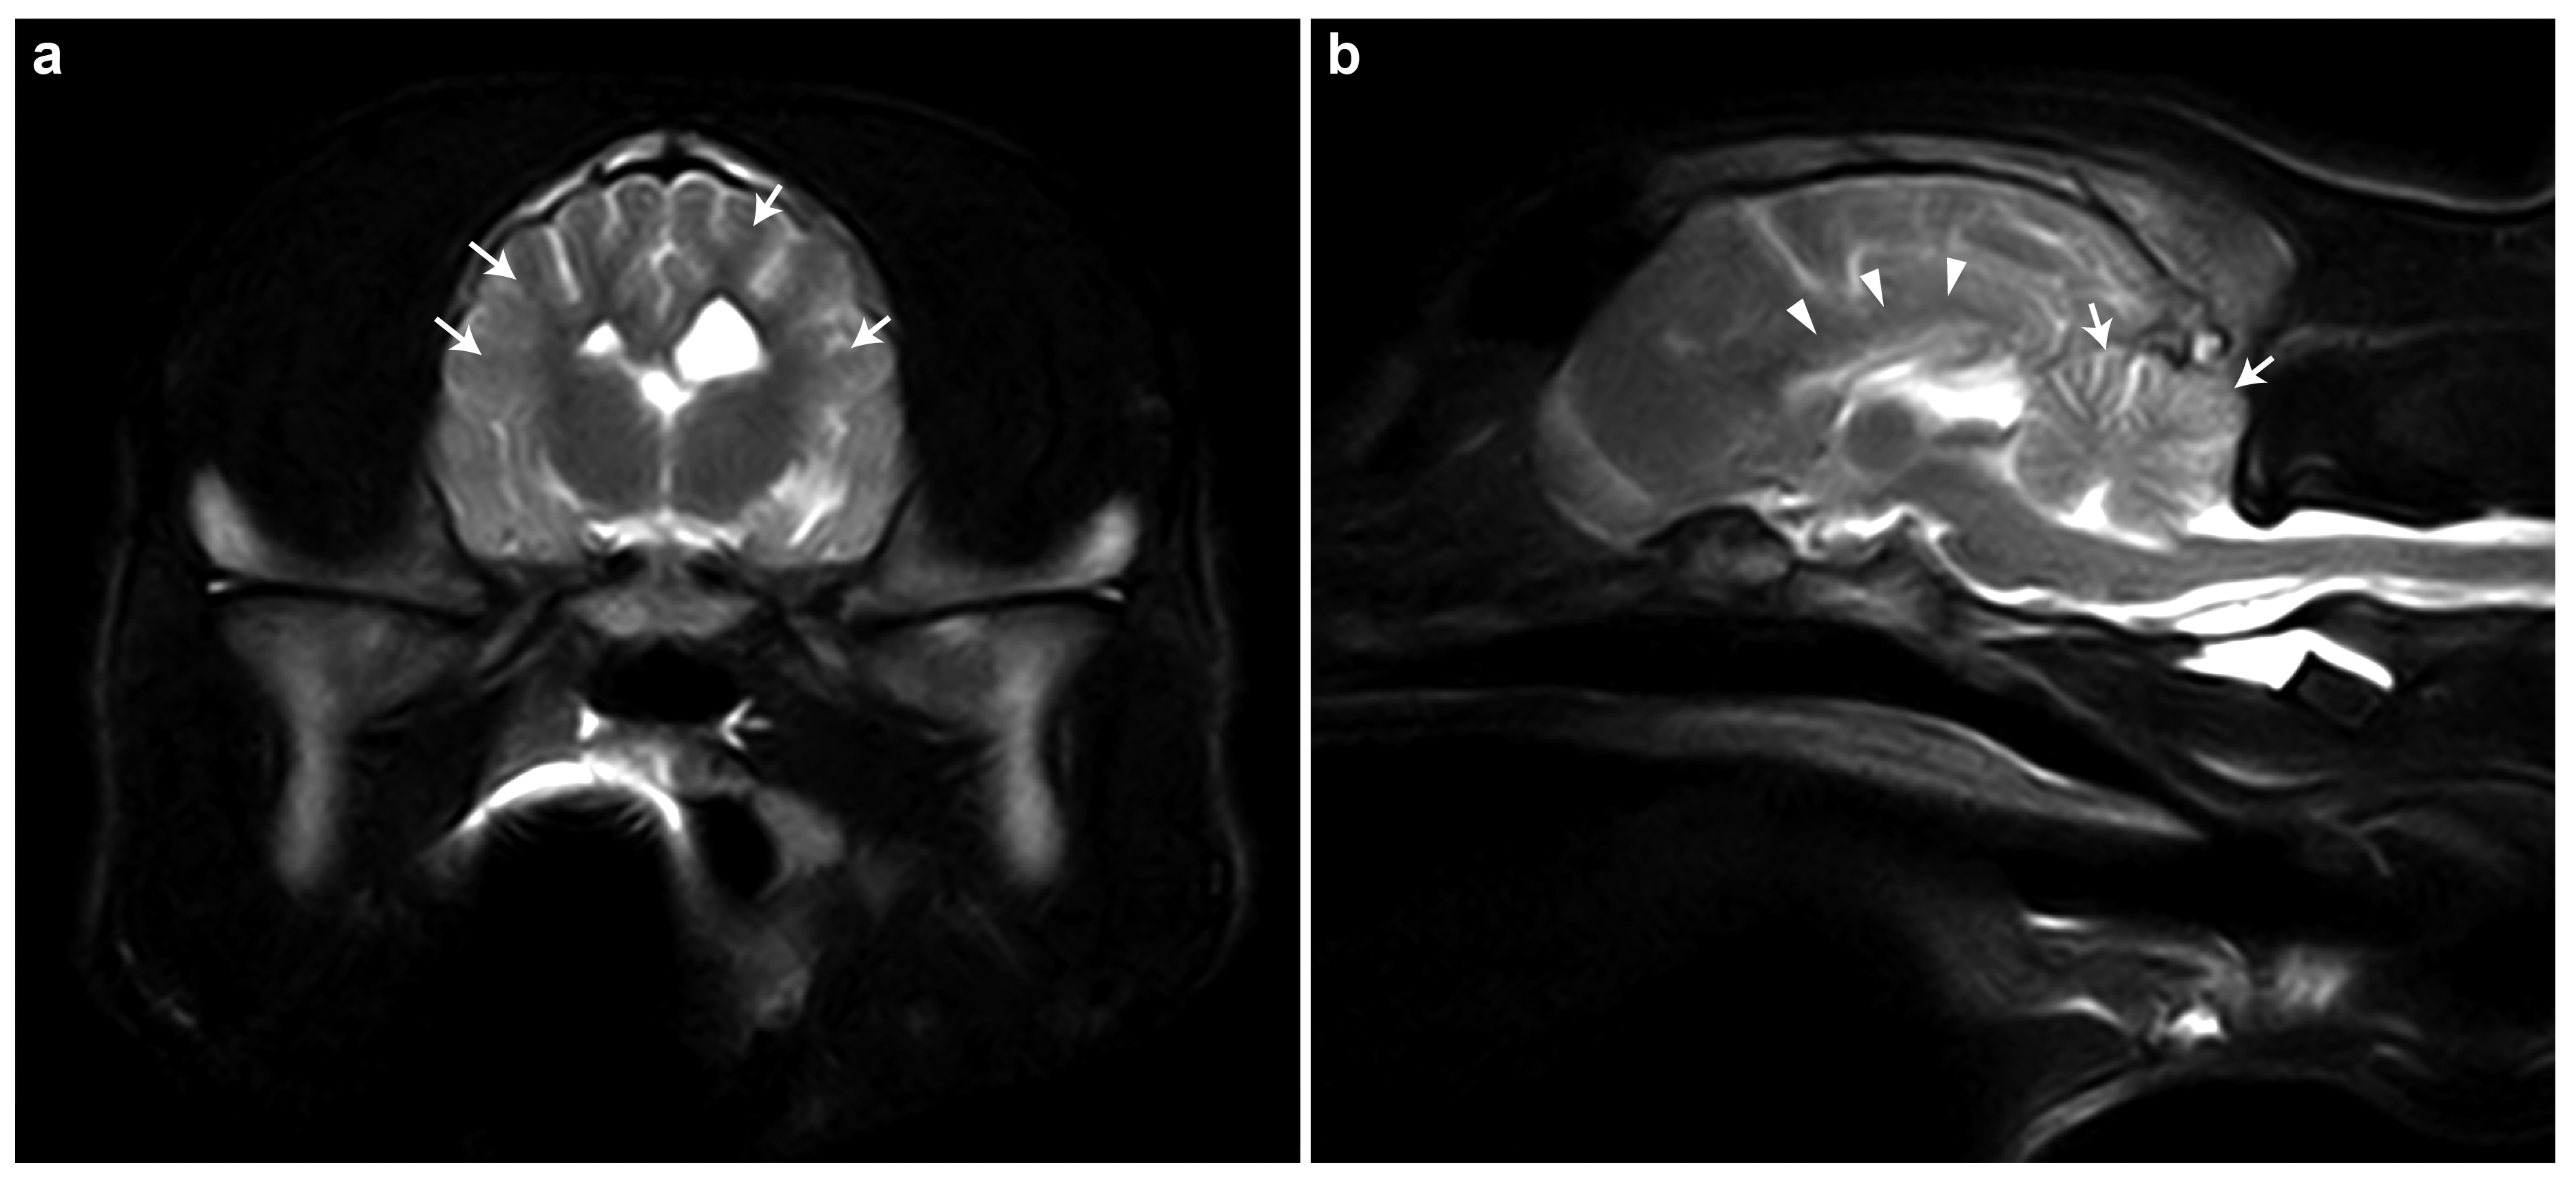

3.1. Clinical Phenotype